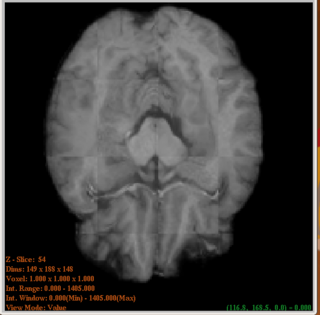

Checker Image of source and target before registration

Checker Image of source and target after registration